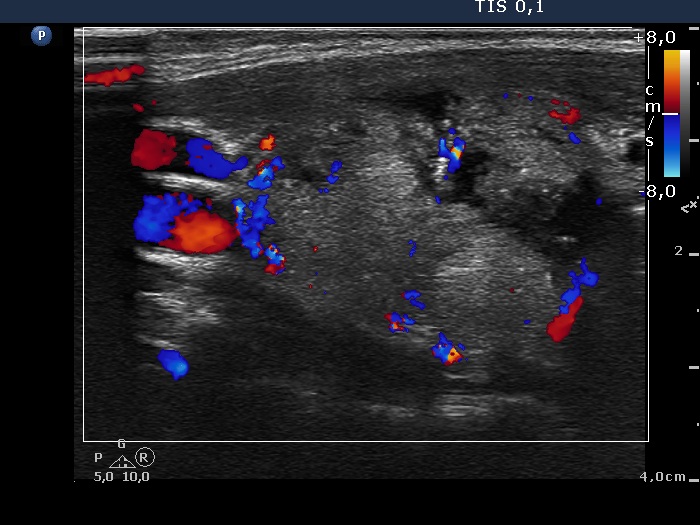

Ultrasonography revealed a large nodule in the right lobe. The upper two third of the lesion was echonormal, inhomogeneous while the lower third of the mass was hypoechogenic and contained microcalcifications. The presence of a perinodular blood flow was doubtful.

FNAC report: follicular tumor.

Combining the US and FNAC results the probability of cancer was greater than the average.

Histopathology: follicular adenoma.